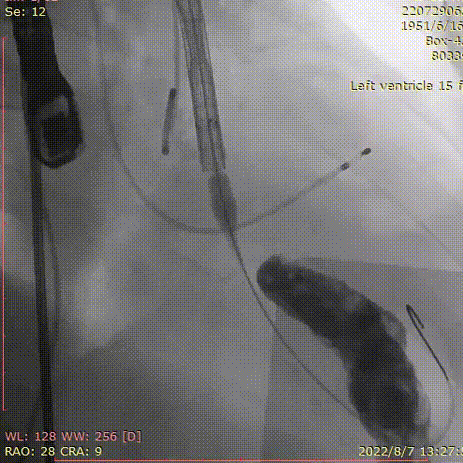

全麻,气管插管,经右侧锁骨下静脉入路放置临时起搏器。

右侧股动脉为主入路,左侧股动脉为辅入路。

直径20mm TaurusAtlas球囊进行预扩,同时预装TaurusElite AV23瓣膜。瓣环下0-2mm开始定位释放。释放过程中多角度造影,超声辅助定位确定瓣膜最终位置。释放后再次造影确定佐证。

心脏外科彭冉主任及周家旺副主任团队行股动脉切开术

20mm球囊预扩张:

球囊有明显腰征,无漏。

术后造影:

大鞘撤出外周血管,造影

术中20mm球囊预扩可见明显腰征,无瓣周漏,左冠充盈速度可。选择TaurusElite  AV23瓣膜送至主动脉弓,输送系统轻松过弓及跨瓣,精准定位无冠窦最低点,利用可回收功能,术中对位置进行适当调整,大大提升了瓣膜精准释放的几率,保证了手术的安全性。